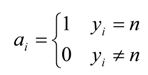

4.3. WP-SVM Performance in Processing Chunk versus Sequential Data

| Inc_Model | INC_SEQ_MODEL | Incremental SVM | |

| Confusion Rate | 1.2 | 1.07 | 1.24 |

| CPU Time | 0.62 | 0.675 | 0.687 |